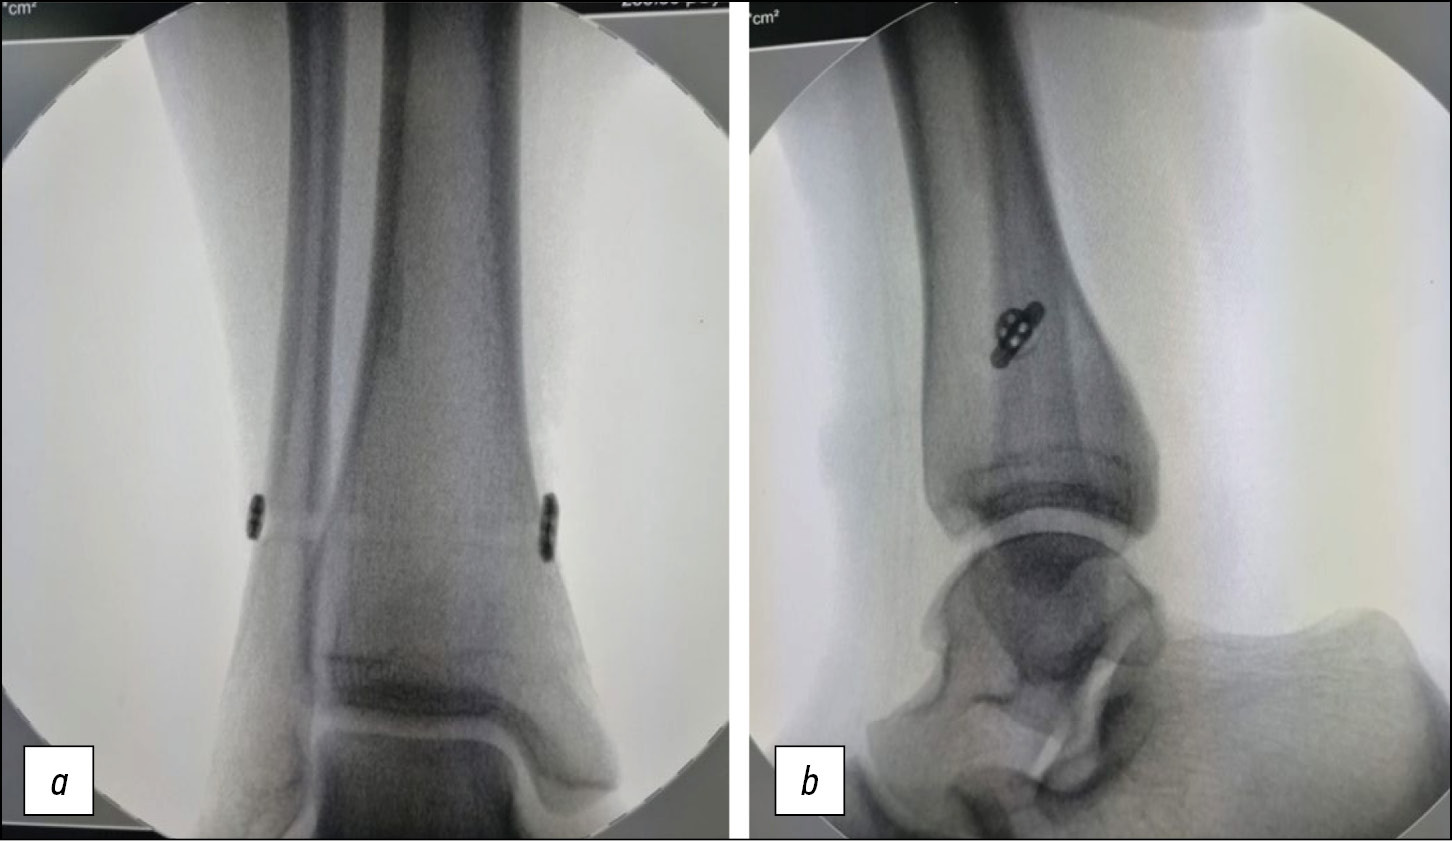

Для уточнения величины и степени смещения свободного костного фрагмента выполнена компьютерная томография (рис. 4). Свободный костный фрагмент оказался бугорком переднего края большеберцовой кости, в связи с его небольшими размерами было принято решение произвести малоинвазивную межберцовую фиксацию синдесмозной системой. Через 4 нед функция конечности полностью восстановилась (рис. 5).

Рис. 5 (a, b). Рентгенограммы голеностопного сустава пациентки А.А. после лечения.

Fig. 5 (a, b). Ankle joint X-rays of patient AA after treatment.